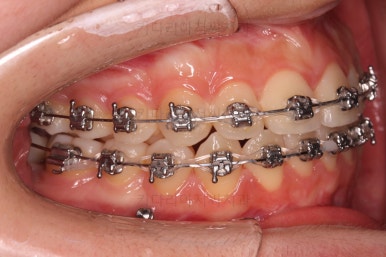

기타 부위들의 디테일을 좀 더 맞춰주고 부산교정 치료를 종료합니다.

전후사진을 비교해 볼게요.

약간의 주걱턱, 돌출입은 고칠 의사가 없어서 그대로 유지하였고 주걱턱 패턴으로 인한 부정교합 부분을 개선했으며 무엇보다 중요한 것은 쓰러져서 많이 썩어있던 치아를 자칫 치료 못할 뻔 했는데 교정치료와 병행하여 훌륭하게 치료를 하여 살려 썼다는 점입니다.

그리고 사랑니 발치 + 충치치료 + 교정치료 모든 것이 키다리아저씨치과 한 곳에서 다 가능하다는 점이 치과의 매우 큰 장점이지요.